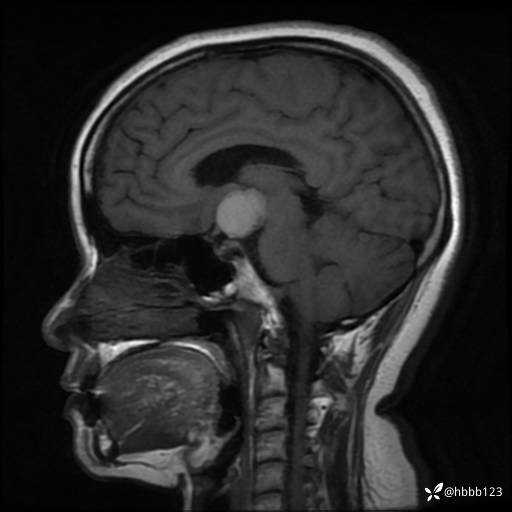

矢状位重建:

T1WI矢状位重建:

T1WI 增强 矢状位重建: